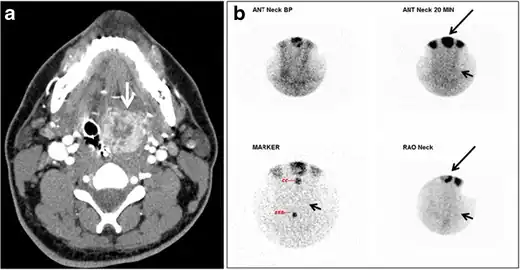

Fig. 8. A 48-year-old male patient post total thyroidectomy with PTC recurrence. a Transverse greyscale ultrasound of the neck demonstrates a left thyroid bed heterogeneous, predominantly hypoechoic irregular lesion with calcifications (white arrow). b A spot image of iodine 123 total body scan of the neck demonstrate a focus of abnormal radiotracer uptake at the left thyroid bed (Black arrows) between the annotated markers. c Enhanced axial CT scan of the neck demonstrates an enhancing large left thyroid bed mass (white arrow) with no calcifications. The lesion exerts a mass effect on the oesophagus (black arrow) and is inseparable from the trachea.[1] -

Fig. 9. A 58-year-old male patient with persistence PTC at thyroid bed with hypervascular nodal metastasis. a–c Transverse greyscale and colour Doppler neck ultrasound demonstrate hypoehoic soft tissue in the left thyroid bed (white arrow in a). There are a heterogeneous enlarged lymph nodes at level 2 and 3 with markedly increased vascularity (white arrow in b and c). d–f Enhanced axial CT images of the neck demonstrate a 2.7 × 1.4 cm hypodense soft tissue lesion anterior to the left carotid sheath (white arrow). There are left-sided enhancing abnormal and enlarged lymph nodes at cervical level 2 and 3 (black arrows).[1]